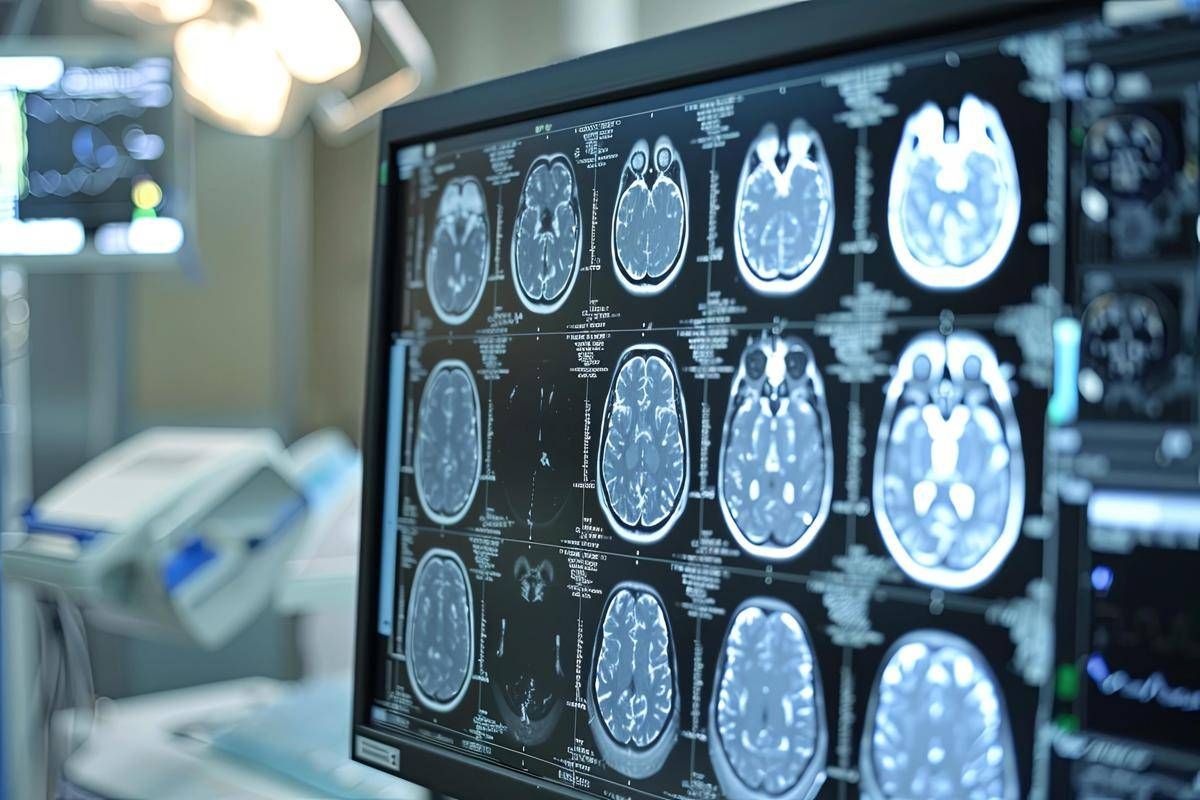

L’ictus rappresenta ancora una sfida di portata globale: ogni anno colpisce circa 12 milioni di persone e nel 20–30% dei casi si tratta di recidive. E’ la seconda causa di morte nel mondo e le recidive spesso comportano esiti ancora più gravi rispetto al primo episodio. Nonostante le terapie oggi disponibili, il rischio di un nuovo evento rimane elevato: 1 sopravvissuto su 5 può andare incontro a un secondo ictus entro 5 anni. “Lo studio Oceanic-Stroke – afferma Andrea Zini, direttore della Neurologia e Rete Stroke dell’Irccs Istituto delle scienze neurologiche dell’ospedale Maggiore di Bologna – segna un cambiamento importante nella ricerca neurologica. Gli inibitori del Fattore XIa come asundexian rappresentano una nuova frontiera nella prevenzione dell’ictus, un passo significativo nella lotta contro le recidive, soprattutto per i pazienti con ictus ischemico non cardioembolico per i quali le opzioni terapeutiche non sono state sostanzialmente innovate negli ultimi anni. Asundexian, primo farmaco di questa classe a completare con successo uno studio di fase 3, potrebbe offrire una soluzione efficace per ridurre il rischio di ictus ricorrenti in questa popolazione. La terapia antiaggregante attualmente in uso non è sufficiente per prevenire completamente i secondi ictus, il che rende l’approvazione di nuovi trattamenti ancora più cruciale”

Asundexian ha ottenuto la designazione fast track dalla Food and Drug Administration degli Stati Uniti come potenziale trattamento per la prevenzione dell’ictus nei pazienti con ictus ischemico non cardioembolico, ricorda la nota. Tuttavia – si legge – va sottolineato che asundexian è ancora un farmaco sperimentale e non è stato ancora approvato da alcuna autorità sanitaria. Lo studio Oceanic-Stroke ha analizzato efficacia e sicurezza di asundexian, inibitore orale del Fattore XIa, somministrato alla dose di 50 mg una volta al giorno, per la prevenzione dell’ictus ischemico in pazienti che avevano recentemente avuto un ictus ischemico non cardioembolico o un attacco ischemico transitorio (Tia) ad alto rischio. Il trattamento è stato valutato in combinazione con la terapia antipiastrinica standard. Si tratta di uno studio multicentrico e internazionale, randomizzato, controllato con placebo, in doppio cieco, a gruppi paralleli e guidato dal numero di eventi, che ha arruolato oltre 12.300 pazienti.